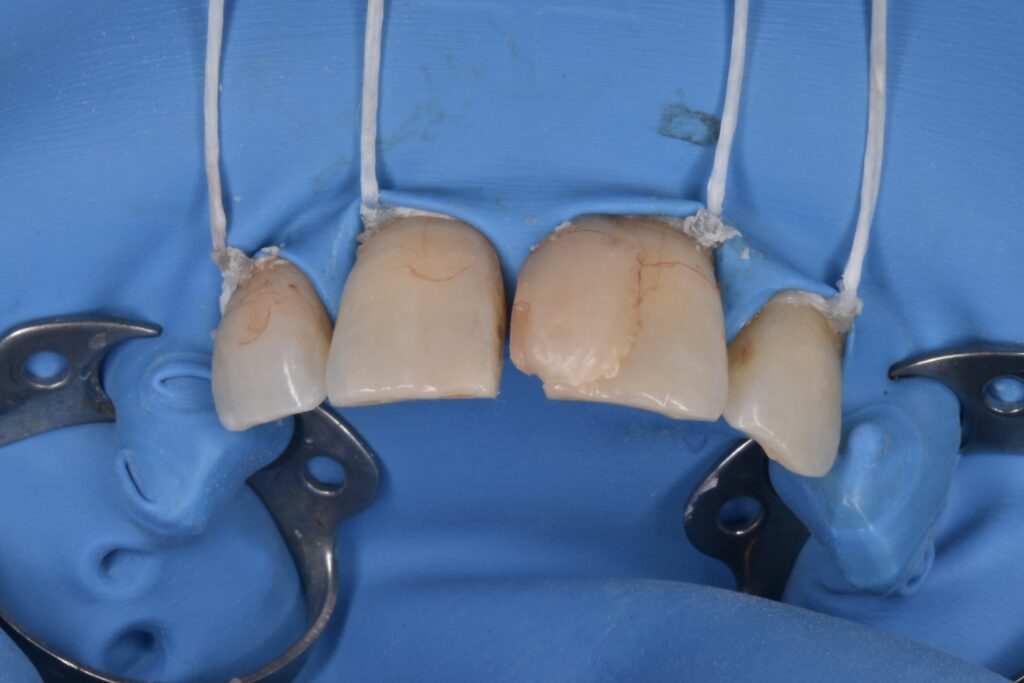

施術中

ダイレクトボンディングの治療は必ずラバーダム防湿を行います。局所麻酔をして行うため痛みはありません。

*他院で行われたダイレクトボンディングの除去はかなり大変です。除去費用として1歯税別5000円頂いております。歯を削らずマイクロスコープを使用して丁寧に除去するためです。